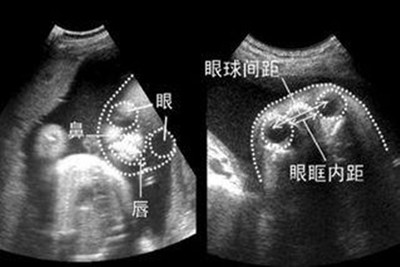

头重脚轻的身体被分成三部分,最后称重。皮肤逐渐呈现出漂亮的红色,皮下脂肪开始平复,逐渐变得不透明。因为皮下脂肪少,所以不会长得很胖。随着骨骼和肌肉的强壮,手臂和腿部的活动变得活跃,然后会感觉到明显的胎动。心脏的活动也是活跃的,可以听到强有力的心音。2.怀孕五个月后的胎儿b超。怀孕五个月后的胎儿头部已占全身长度的三分之一,耳朵的入口是敞开的;牙龈开始形成;皮肤红润透明,可见皮下血管;开始长出胎毛,胎毛,眉毛,指甲。

从怀孕五个月的b超图像中,可以清楚地看到胎儿的耳朵已经微微张开,头发和眉毛已经开始生长,牙龈也开始形成。手指和脚趾开始鼓胀,长出指甲。有时候,他喜欢把手放进嘴里,感觉手上的味道是人间美味。一般来说,五个半月的胎儿体重在250克左右,而身高在16.517cm左右,双顶径平均4.88 cm,腹围平均14.80 L。

通过检查发现孩子的发育符合月数就够了,不必太在意肚子的大小。另外,你想知道如何让胎儿长大。其实只要你营养没问题,孩子会自己长大的。1.怀孕五个月后的胎儿发育:此时胎儿头部已占全身长度的1/3,耳朵的入口是敞开的;牙龈开始形成;头发眉毛都完成了。指甲里长出手指和脚趾,呈凸起状,宝宝会用嘴舔吸大拇指,就像在品尝手指的味道。